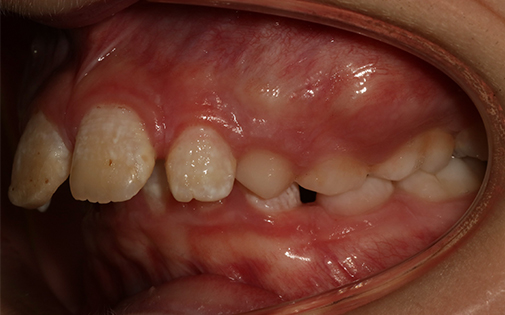

This teenage patient had a very crowded top left canine tooth as well as an underbite. He was successfully treated with Invisalign clear aligners in 22 months.